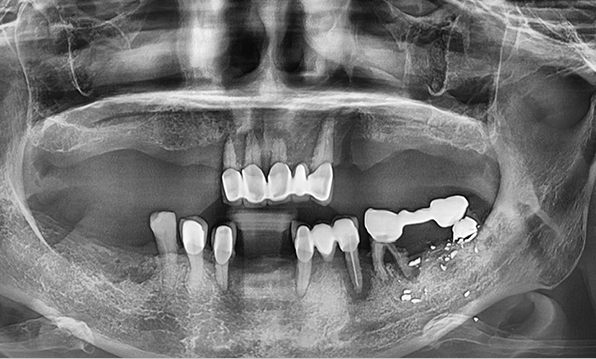

Before & After

| Before | After |